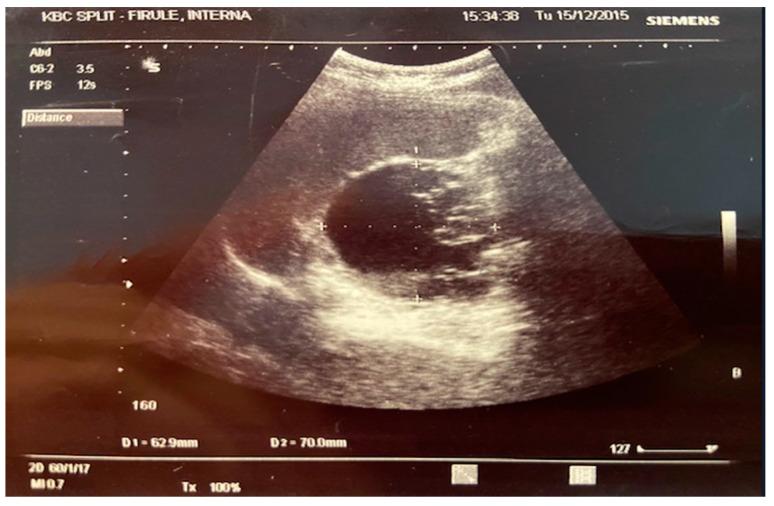

Thrombotic microangiopathy (TMA) is a category of diseases consisting of thrombocytopenia, microangiopathic haemolytic anaemia, and widespread occlusive microvascular thrombosis. We report two cases of a thrombotic microangiopathic syndrome associated with non-invasive mucinous cysts and mucinous adenocarcinoma. TMA was treated in both cases by surgical removal of the tumours. We hypothesise that mucin secretion in the case of non-invasive mucinous cysts and paraneoplastic secretion of antibodies in the case of mucinous adenocarcinomas are the causes of endothelial damage with thrombocytopenia and microangiopathic haemolytic anaemia. Finally, patients with TMA who exhibit unusual clinical characteristics or weak responses to plasma exchange should be examined for an underlying tumour. Tumour treatment is the preferred therapy for tumour-associated TMA.

血栓性微血管病(TMA)是一类由血小板减少、微血管病性溶血性贫血和广泛的闭塞性微血管血栓形成组成的疾病。我们报告了两例与非侵袭性黏液囊肿和黏液腺癌相关的血栓性微血管病综合征病例。两例均通过手术切除肿瘤来治疗TMA。我们推测,非侵袭性黏液囊肿情况下的黏液分泌以及黏液腺癌情况下的副肿瘤性抗体分泌是导致内皮损伤并伴有血小板减少和微血管病性溶血性贫血的原因。最后,对于具有不寻常临床特征或对血浆置换反应不佳的TMA患者,应检查是否存在潜在肿瘤。肿瘤治疗是肿瘤相关性TMA的首选治疗方法。